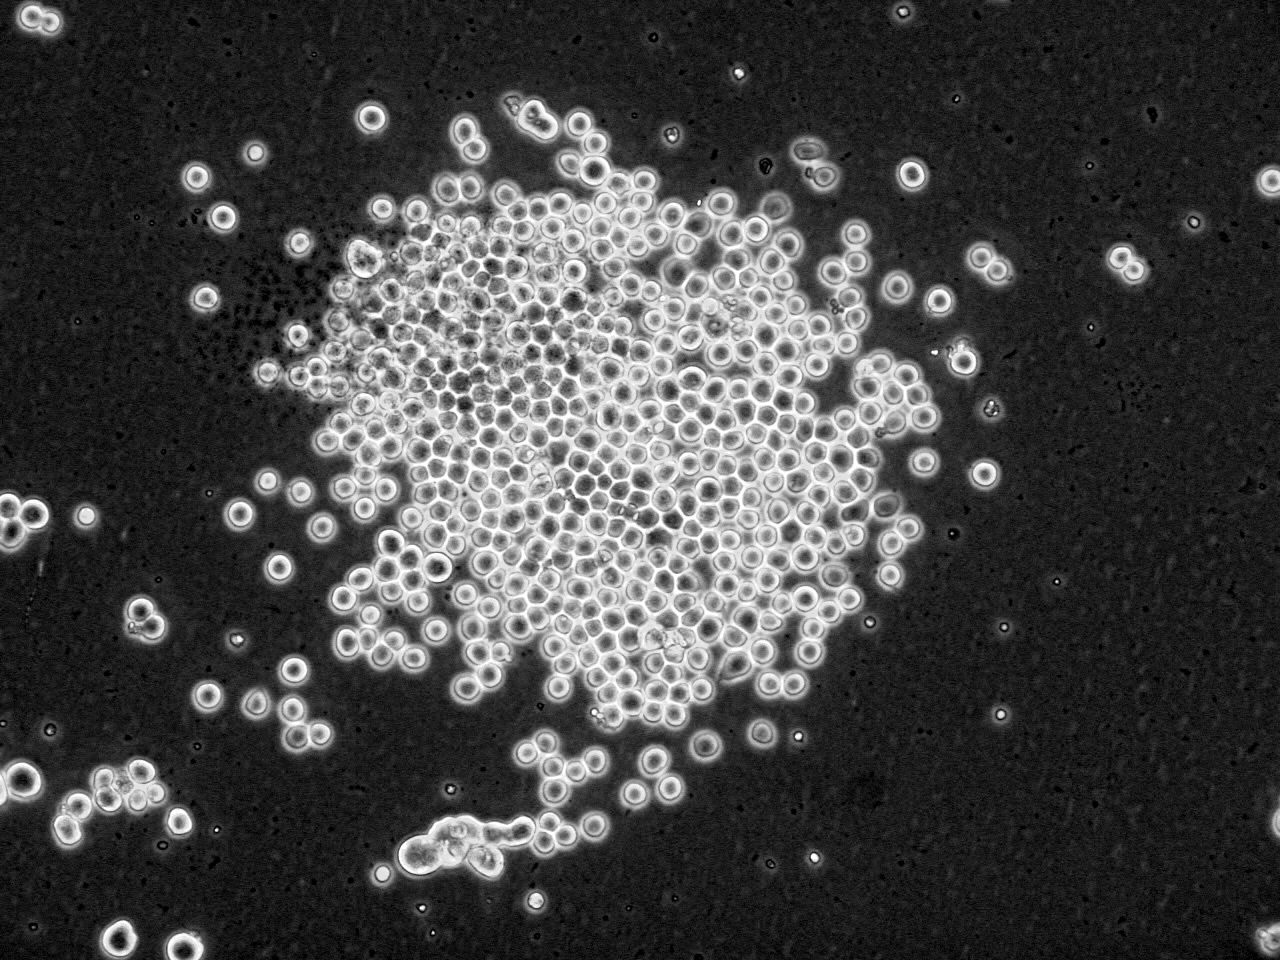

用 以 製 造 戊 型 肝 炎 疫 苗 的 昆 蟲 細 胞

香 港 科 技 大 學 ( 科 大 ) 與 北 京 綠 竹 生 物 製 藥 有 限 公 司 合 作 研 發 戊 型 肝 炎 疫 苗 , 首 次 利 用 獨 特 的 昆 蟲 細 胞 系 統 和 方 法 來 生 產 免 疫 原 蛋 白 , 為 影 響 全 球 三 分 一 人 口 的 傳 染 病 尋 求 預 防 方 法 。 這 項 世 界 首 創 的 疫 苗 技 術 由 科 大 生 命 科 學 部 謝 雍 教 授 帶 領 團 隊 研 發 , 能 簡 化 生 產 程 序 及 降 低 生 產 成 本 。

戊 型 肝 炎 病 毒 ( HEV ) 感 染 是 一 個 重 要 的 公 共 衞 生 問 題 , 在 世 界 許 多 地 區 造 成 急 性 肝 炎 的 大 爆 發 。 研 發 出 有 效 預 防 戊 型 肝 炎 的 疫 苗 迫 在 眉 睫 , 北 京 綠 竹 生 物 製 藥 有 限 公 司 於 2010 年 5 月 和 香 港 科 技 大 學 研 究 開 發 公 司 簽 訂 了 合 作 開 發 研 製 戊 型 肝 炎 疫 苗 的 協 議 , 2010 年 9 月 啟 動 該 項 目 , 經 過 一 年 半 的 努 力 , 科 大 謝 雍 教 授 帶 領 的 團 隊 終 於 建 立 了 用 昆 蟲 細 胞 表 達 戊 型 肝 炎 病 毒 疫 苗 的 創 新 系 統 , 臨 床 前 研 究 工 作 正 在 按 計 劃 進 行 , 目 前 進 展 順 利 。 科 大 和 綠 竹 建 立 的 獨 特 表 達 系 統 和 方 法 , 能 夠 直 接 和 高 效 地 表 達 病 毒 抗 原 , 這 在 世 界 上 屬 首 創 , 並 且 由 於 產 生 的 抗 原 容 易 回 收 , 大 大 簡 化 生 產 程 序 , 降 低 生 產 成 本 , 得 到 更 能 被 廣 大 群 眾 所 接 受 的 產 品 。 它 的 特 點 是 用 昆 蟲 細 胞 能 夠 表 達 比 較 長 的 蛋 白 片 段 , 使 其 包 括 更 多 的 抗 原 決 定 簇 , 尤 其 是 T 細 胞 的 抗 原 決 定 簇 ; 昆 蟲 細 胞 表 達 的 蛋 白 折 疊 方 式 更 接 近 於 天 然 蛋 白 , 這 些 優 點 都 表 明 其 表 達 的 蛋 白 免 疫 原 性 較 強 。